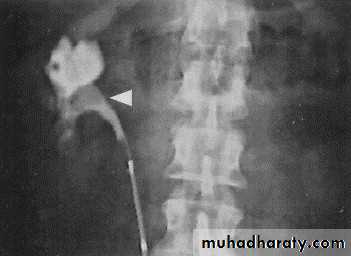

l.V.U. findings:

-Plain film may be useful in demonstrating calculi.-After contrast injection:

Acutely obstructed kidney shows a dense nephrogram (dense opacification of the renal parenchyma).excretion of contrast (opacification of the collecting system which may take many hours), then the level and degree of obstruction can be determined as dilated pelvi-caliceal system and ureter are followed down to the point of obstruction (point of hold up).

Pyeloxinus reflux may result from rupture of a fornix precipitated by contrast-induced diuresis superimposed on the increased hydrostatic pressure of an obstructed pelvicaliceal system. Urine and contrast extravasate into the renal sinus and perirenal space